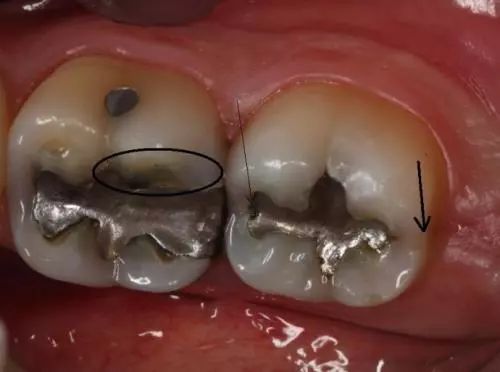

2.牙隐裂——*毒冰**会使服用者感到焦虑、亢奋或紧张,从而导致磨牙。你能看到他们的牙齿上有明显的磨耗痕迹。有时候就算是吃一些很软的食物(如土豆泥),也会使服用者的牙齿出现隐裂。

3.龋齿——*毒冰**成瘾者会因为口干反应而渴望吃含糖量高的食物和饮品。这样,口腔内靠糖类为生的细菌会大量繁殖,并分泌酸性物质,使牙齿损坏更严重。*毒冰**服用者的龋齿通常会从牙龈边缘发展到整个牙齿,前牙首当其冲。

4.牙周病——*毒冰**成瘾者通常不会定期做口腔检查,口腔保健的缺乏会引发牙周病。同时,牙齿和牙龈都需要血液来保持健康,*毒冰**使口腔组织的血管收缩,血流量减少,最终导致口腔组织坏死。

1.吸毒者出现龋齿。

3.吸毒者龋齿呈严重趋势。

1.吸毒者龋齿发展到牙龈边缘以下。